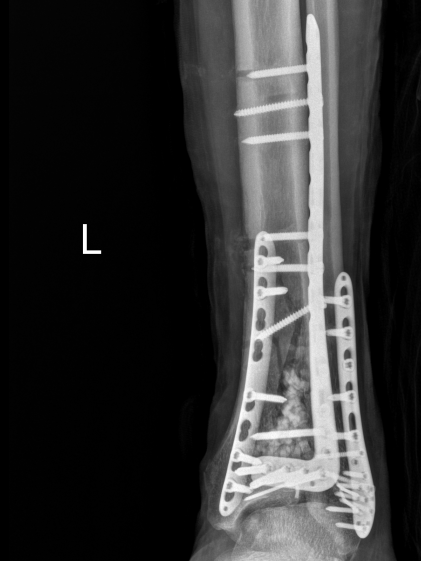

3月20日,急诊外科团队实施了左胫腓骨远端骨折切开复位内固定术,成功复位骨折、稳固固定,恢复左下肢正常力线。

骨折终极固定术后复查影像3月25日,距离入院整整27天,在多学科团队的日夜坚守下,患者顺利转出ICU,进入普通病房接受康复治疗。转出前,患者意识清醒、精神良好,已停用所有血管活性药物,呼吸、循环稳定,血氧饱和度持续99%,双肺无明显感染体征,曾经濒临崩溃的生命重焕生机。